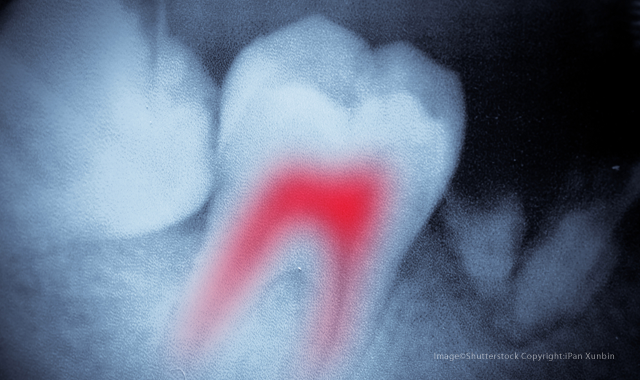

The new method of detecting bacteria during root canal treatments could eliminate secondary infections and the need for follow-up visits.

Root canals are bad enough without the threat of secondary infection and multiple follow-up visits. Now, thanks to a new device, researchers believe they can eradicate the need for numerous appointments-and cut down on treatment failure.

Since approximately a quarter of root canals fail over time due to secondary infections, the ability to detect potentially hazardous leftover bacteria at the time of treatment could be extremely beneficial. It could also cut down on the number of visits, as most procedures currently require one or two secondary visits to the dentist. The new device, called SafeRoot, was created to detect any remaining bacteria at the completion of root canal treatment to reduce the need for reintervention or extraction